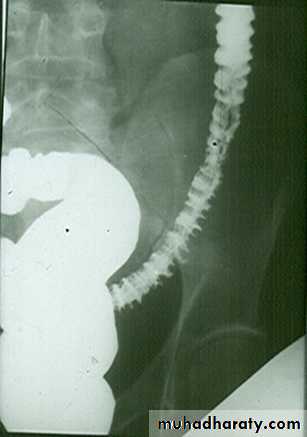

Radiological finding of CD in BA follow through :

• _Multiple mucosal ulcers aphthous ulcers.• _Transmural ulcer (Rose thorn appearance )

• _longitudinal fissures

• _Multiple skip lesions

• _when severe leads to cobblestone appearance

• _May lead to sinus tracts and fistulae

• _widely separated loops of bowel due to fibro-fatty proliferation

• _Thickened folds due to edema.

• _Pseudo diverticula formation: due to contraction at the site of ulcer with ballooning of the opposite site.

Crohns disease

CD